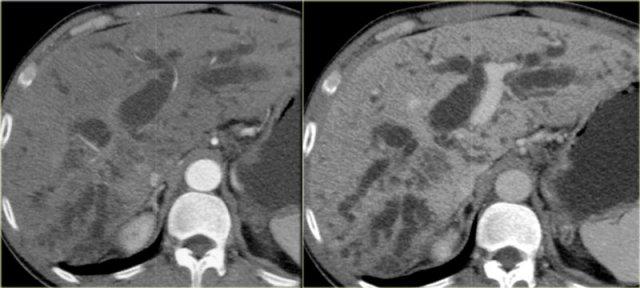

Các dấu hiệu CT giai đoạn muộn được thấy trong các hình ảnh bên trái.

Hãy quan sát các hình ảnh rồi tiếp tục đọc.

Các dấu hiệu bao gồm:

- Thay đổi hình thái xơ gan (mất thể tích thùy phải và thùy đuôi to ra (mũi tên))

- Giãn đường mật rõ hơn

Chụp đường mật được sử dụng trong chẩn đoán ban đầu của bệnh khi chỉ có các chỗ hẹp tinh tế, và ở những bệnh nhân đã biết mắc PSC để tìm kiếm các chỗ hẹp mới nghi ngờ ung thư.

Trên hình ảnh chụp đường mật, chúng ta có thể thấy:

- Hình chuỗi hạt (Beading): hình ảnh xen kẽ giữa các chỗ hẹp và các đoạn ống mật bình thường hoặc giãn nhẹ

- Hình cây trụi lá (Pruned-tree): các ống mật ngoại vi bị hẹp và khó quan sát

- Bờ thành không đều (Mural irregularity): bờ lòng ống không đều (thấy rõ nhất ở bên trái trong ống mật ngoài gan)

- Túi thừa (Diverticula): thấy rõ nhất ở bệnh nhân tiếp theo

Bên trái là các dấu hiệu điển hình trong PSC.

Lưu ý các túi thừa trong hình bên phải.

Túi thừa có tính đặc hiệu rất cao cho chẩn đoán PSC.

Vì vậy, khi phát hiện các túi thừa này, bạn cần tìm kiếm ngay các chỗ hẹp tinh tế ở các ống mật trong gan.